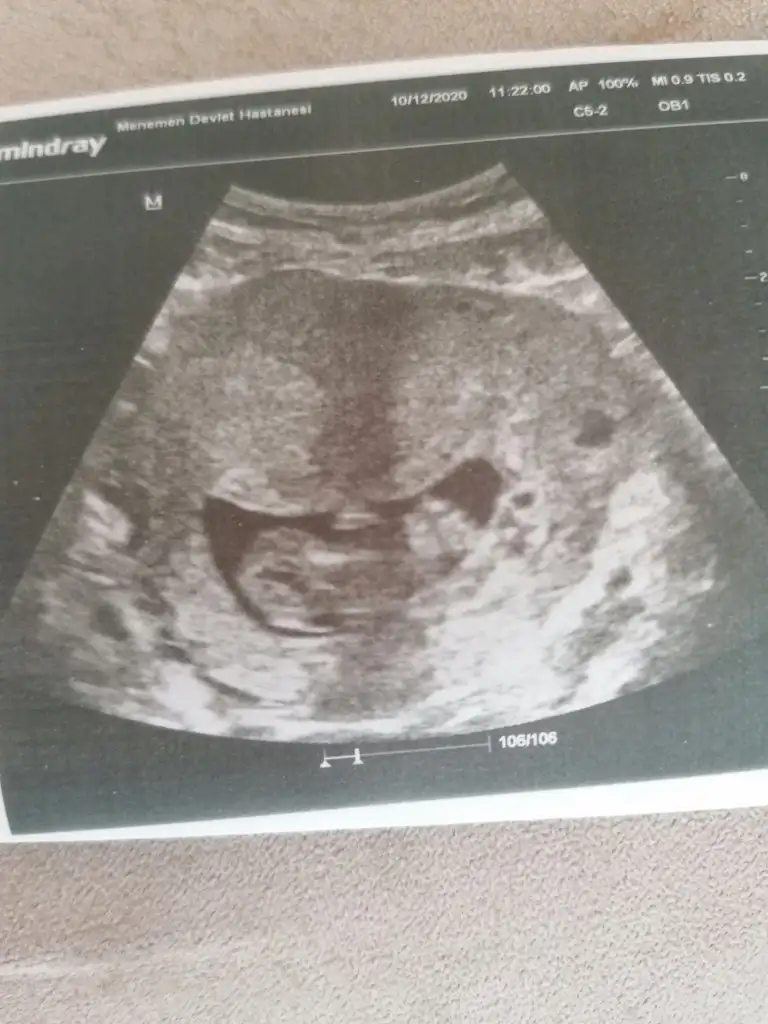

merhabalar banada yorum yapabilirmisiniz foto 12+4 tü şuan 15. haftadayım 2 oğlum var bu 3 cü olacak inşallah cinsiyetini çok merak ediyorum rabbim ilk önce sağlık versin

Malesef başka görüntüm yok ilk kız siz dediniz inşallah öyledir 🤲🤲🤲🤲 bir hafta sonra randevum var ozaman yazarım foto yollarım

Bir hafta nasıl dayanacaksin, ben dayanamazdım, yani dayanırım da düşün düşün bir hal olurdum. :) prenses geliyordur insallah :)